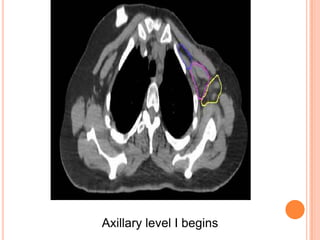

Axillary level I begins